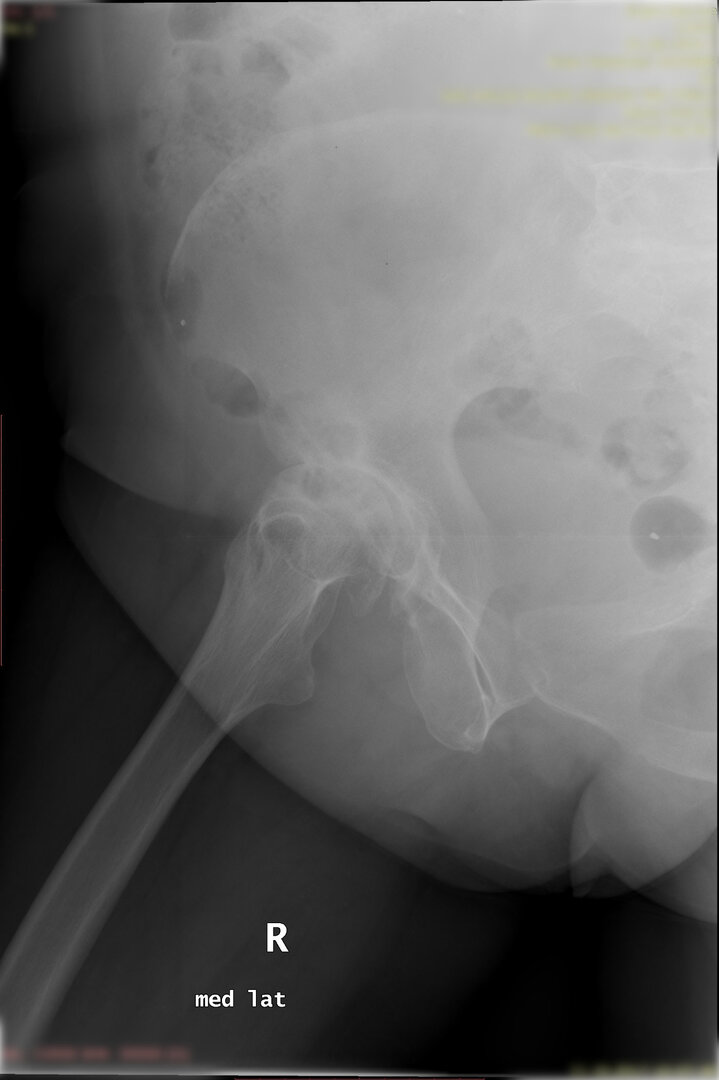

Peki kalça protezi ameliyatın da neler yapıyoruz? Diz protezi ameliyatındaki benzer aşamaları uyguluyoruz. Kalça eklemi dize göre yapısal olarak ve çalışma sistemi olarak farklıdır. Kalça eklemi bir yuva ve onun içinde hareket eden femur başı dediğimiz bir toptan oluşur. Kalça eklemi kireçlenmesinde bu baş ve yuva yüzeyindeki kıkırdakların aşınması sonucu başın yuvarlaklığı kaybolur, sonuçta ağrı ve hareket kısıtlılığı ortaya çıkar. Bu yüzeyleri değiştirirken öncelikle bu başı kesip atıyoruz. Daha sonra yuvayı yine kılavuzlarla oyup uygun büyüklükteki protezi sıkıştırdıktan sonra en az 2 vida ile kemiğe adapte ediyoruz. Daha sonra alt uyluk kemiğini yine kılavuzlar yardımı ile oyduktan sonra kemiğe adapte ediyoruz ve sistemi birleştiriyoruz.

Büyütmek için üzerine tıklayınız.